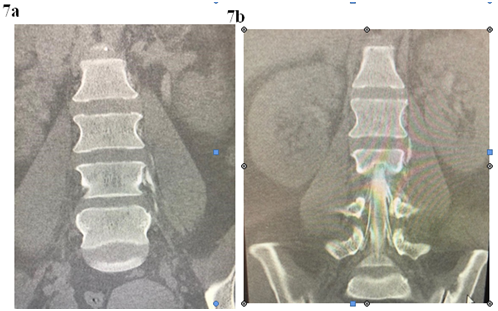

Her imaging showed multiple foraminal cysts; see in Figure 6.

Figure 6 Myelogram of the spine shows multilevel, at times bilateral Tarlov Cysts.

The left L 2/3 nerve root sleeve demonstrates an intra- foraminal Tarlov cyst measuring approximately 7mm indiameter with active extravasation of contrast in the surrounding tissues along the left para spinal muscles.

L 1/2 nerve root sleeve demonstrates bilateral small Tarlov’s cysts, the cyst on the left measures up to 4mm in diameter; the right measures up to 2.5mm in diameter; see Figures 7a & 7b.

Figure 7a & 7b Myelogram: Extravasation of contrast into the paravertebral soft tissue around the left lumbar 2/3 Tarlov cyst suggesting a CSF leak at this level.